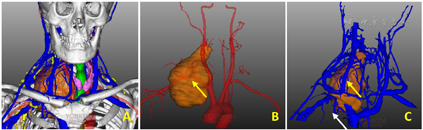

影像学检查:CT平扫+增强:右颈部胸锁乳突肌内侧肌间隙内肿瘤性病变,大小约166 mm×85 mm,考虑神经纤维瘤可能;由右锁骨下动脉及右侧椎动脉供血,右颈总动脉、气管及临近结构向左移位。右锁骨下动脉及颈内静脉被肿瘤紧密包绕(图2)。MR平扫+增强显示:肿物与C6-T2右侧椎间孔关系密切,考虑神经纤维瘤可能,右锁骨下动脉及右侧椎动脉供血。我们通过提取术前薄层CT增强数据,通过Mimics V20.0(比利时Materialise公司)软件重建患者肿瘤及邻近组织的三维立体图像,从而更直观观察肿瘤大小、形态以及规划手术切除方案(图3)。